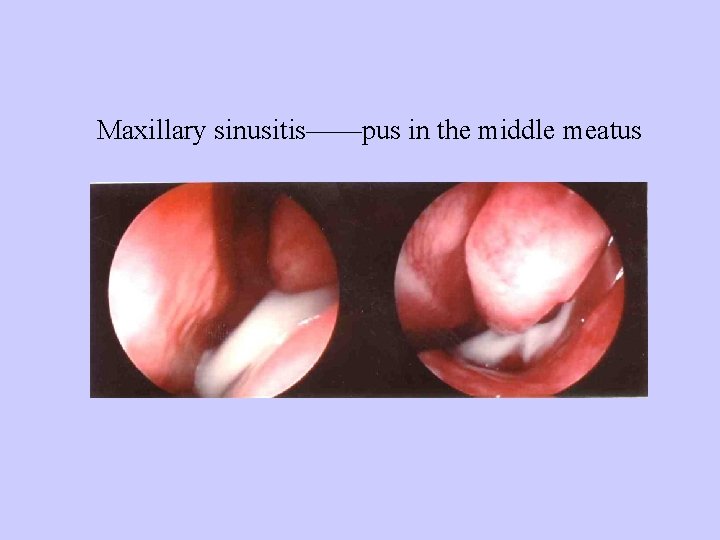

Maxillary sinusitis——pus in the middle meatus